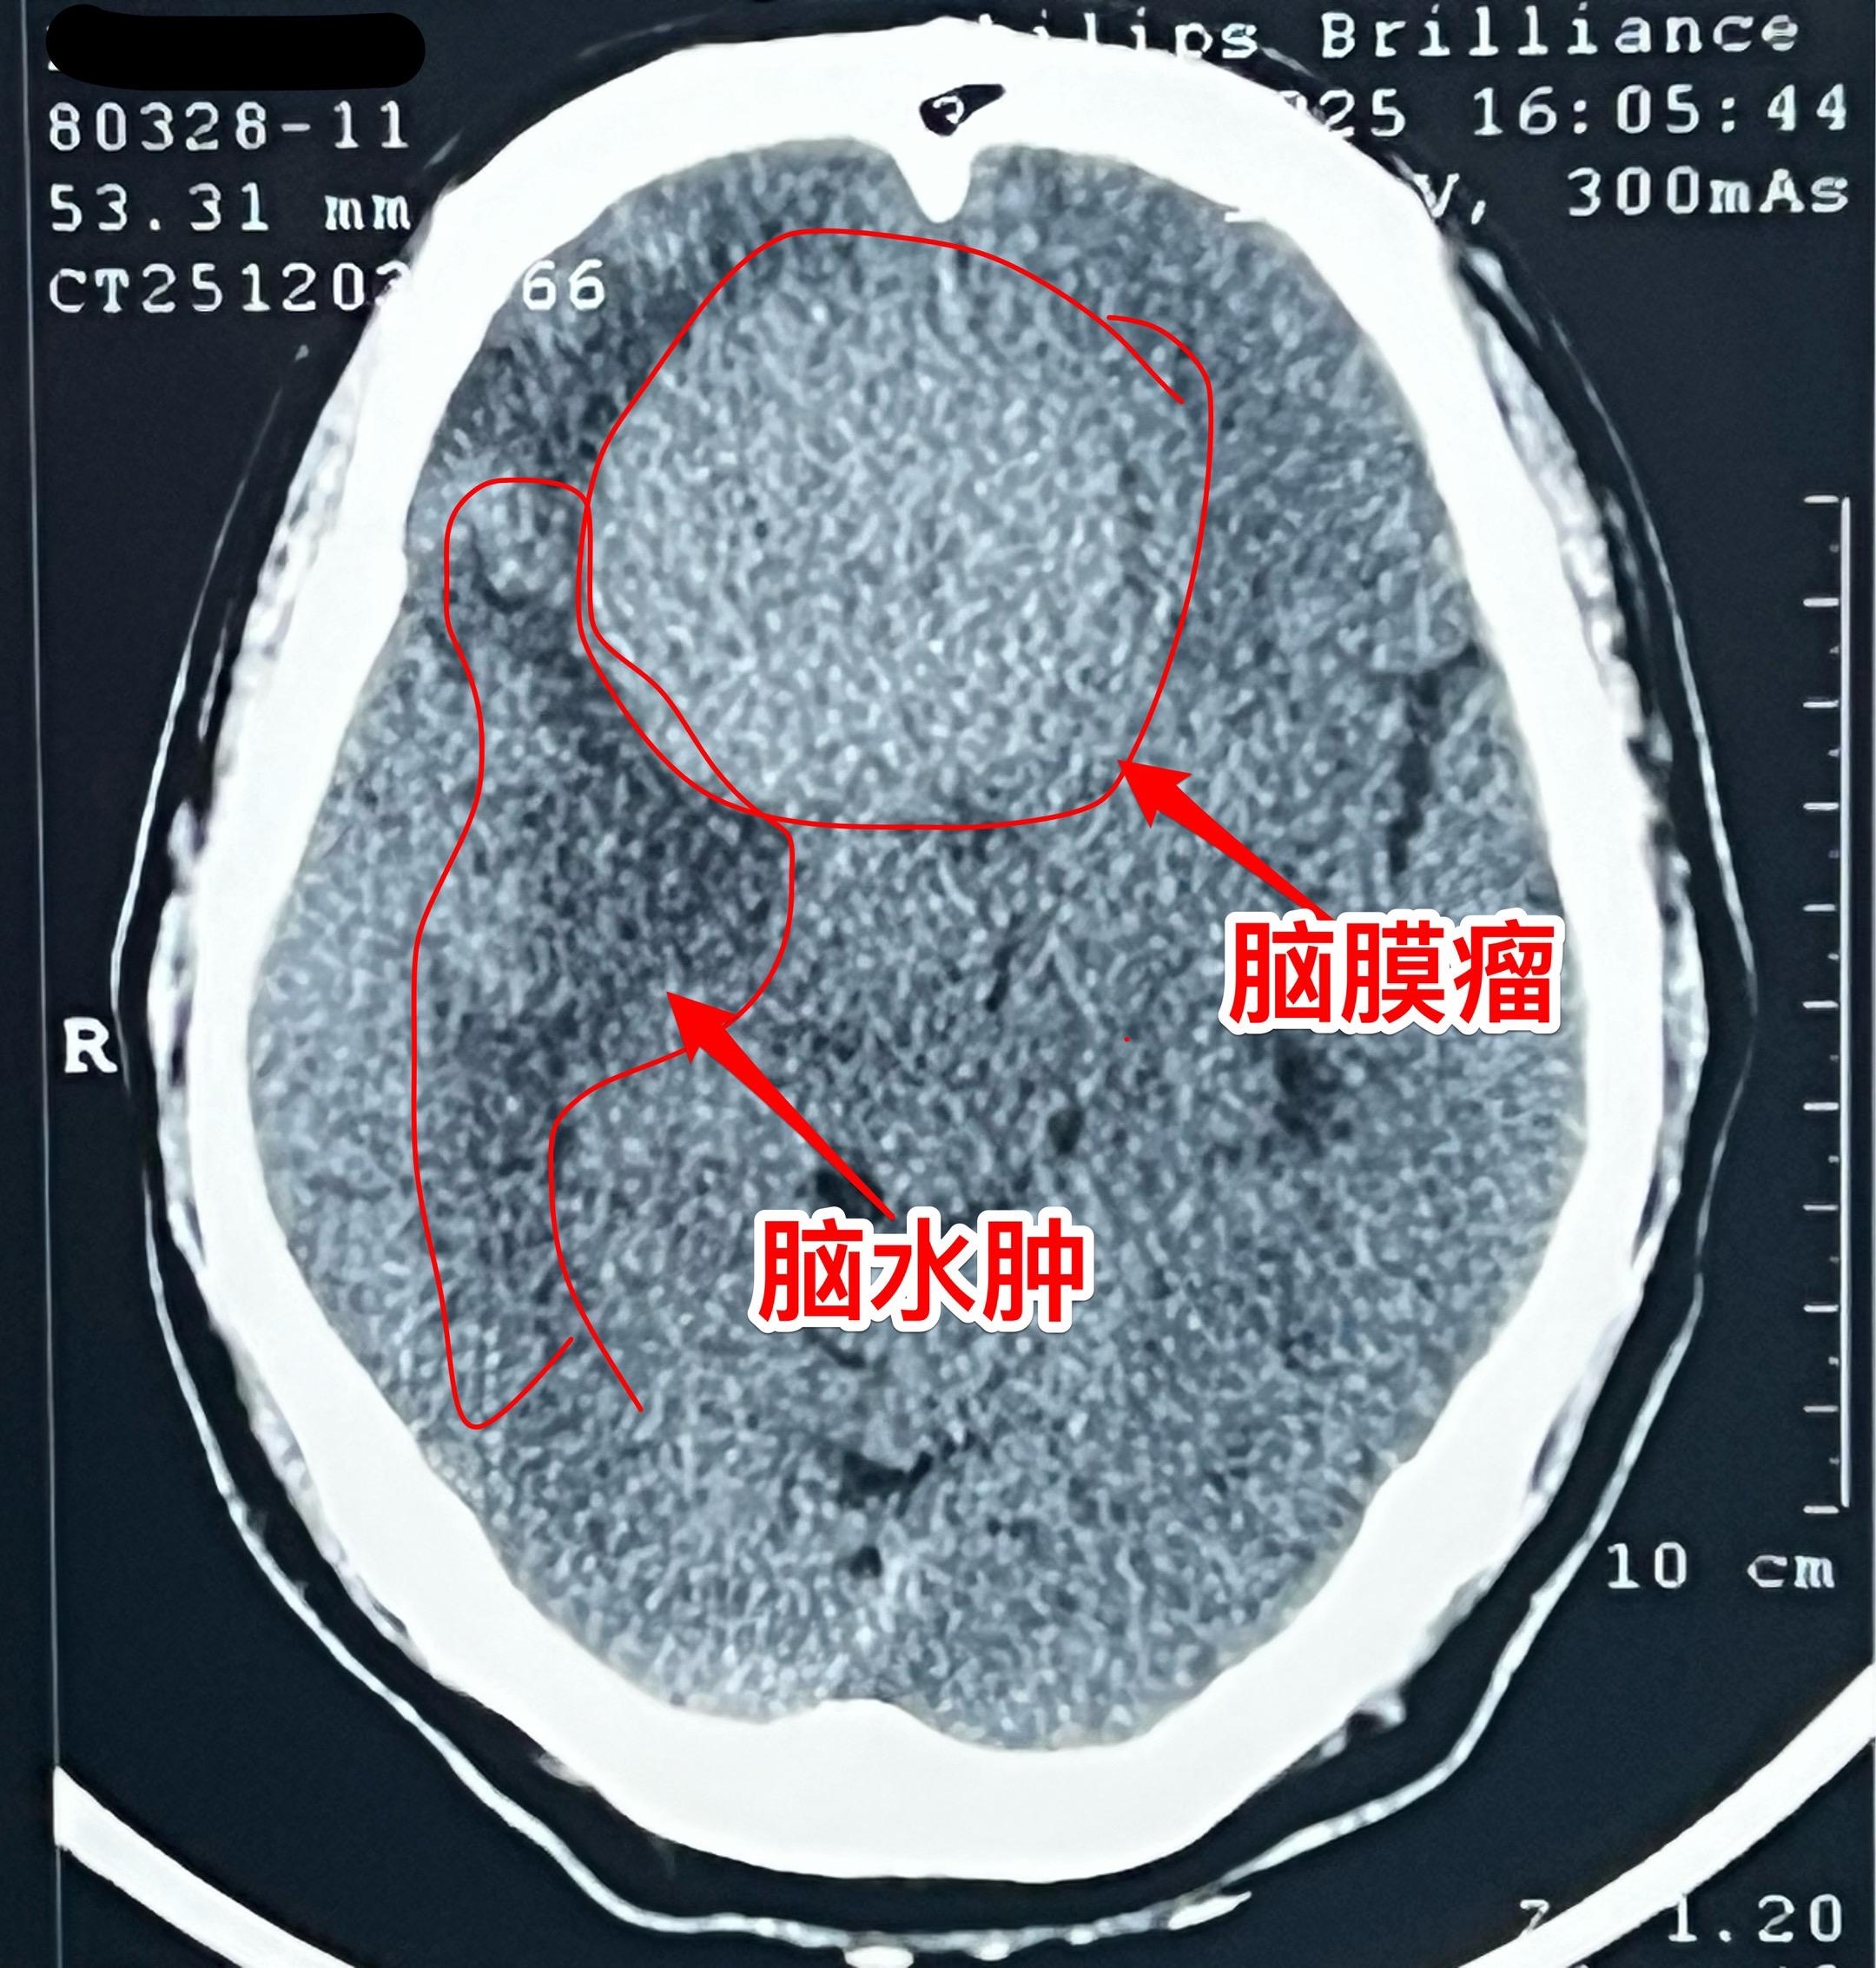

脑膜瘤长在不同的部位产生的症状也不同!这个59岁的内蒙古男性,最开始的症状是右眼视力下降,他认为与糖尿病有关,没有作详细检查。今年出现头痛症状,后来又出现左腿无力症状,他自认为是脑梗塞。症状越来越严重,还发现了嗅觉丧失症状。医生建议行脑部磁共振检查,作了磁共振之后就发现了这个巨大肿瘤。 这个脑膜瘤位置靠近嗅神经、视神经,所以导致视力下降和嗅觉丧失,同时肿瘤导致右侧大面积的脑水肿,造成左腿无力。手术后这些症状有望好转。